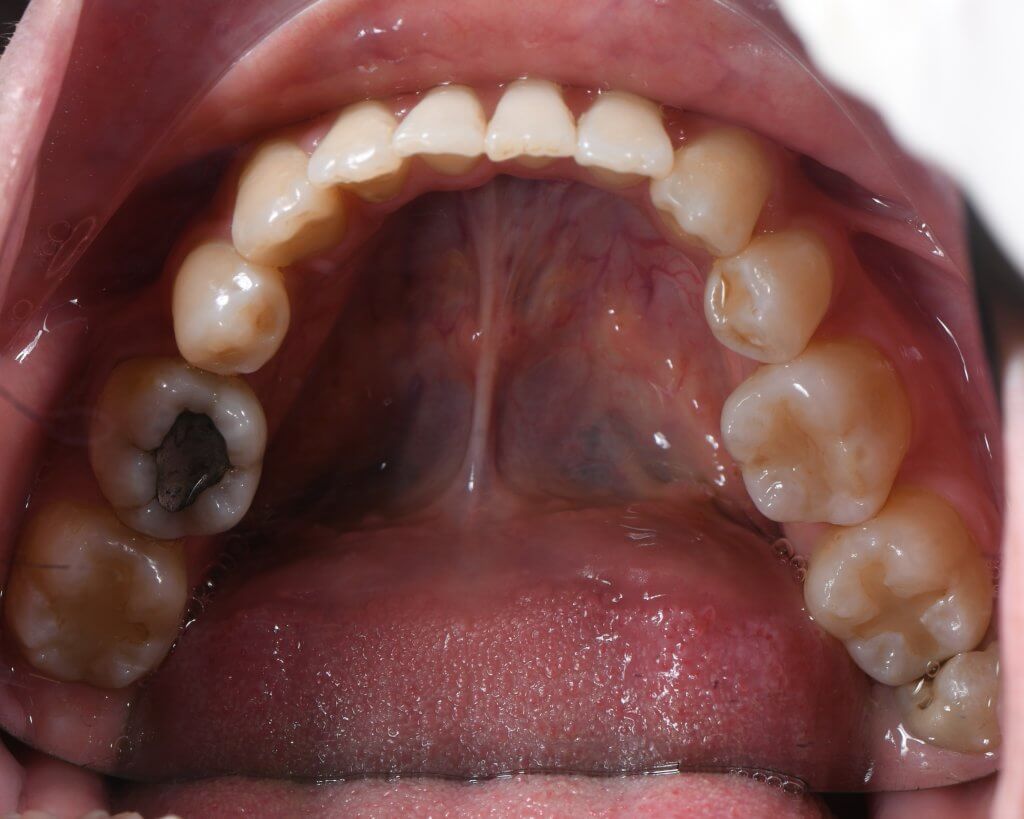

為了騰出足夠的後退空間以改善嘴突,我們決定拔除四顆第一小臼齒。治療核心在於「錨定控制」:

- 上顎後收: 利用後方大臼齒作為錨定點收回前牙,同時配合頭帽(Headgear)提供額外的垂直向力量,除了能有效壓入前牙改善笑齦,更能防止門牙在後退過程中發生過度內傾(Tipping)的問題。

- 下排排齊: 利用拔牙後的空間將擁擠的下齒列重新排列,並同步往後收納。